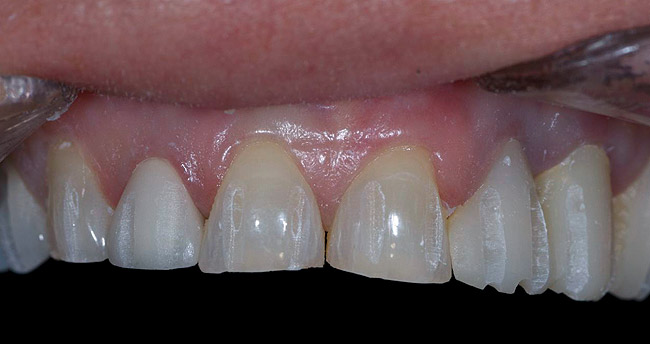

Figure 3  Preoperative view. Note the worn incisal edges and end-on-end occlusal relationship requiring an increase in OVD to restore.

Figure 3